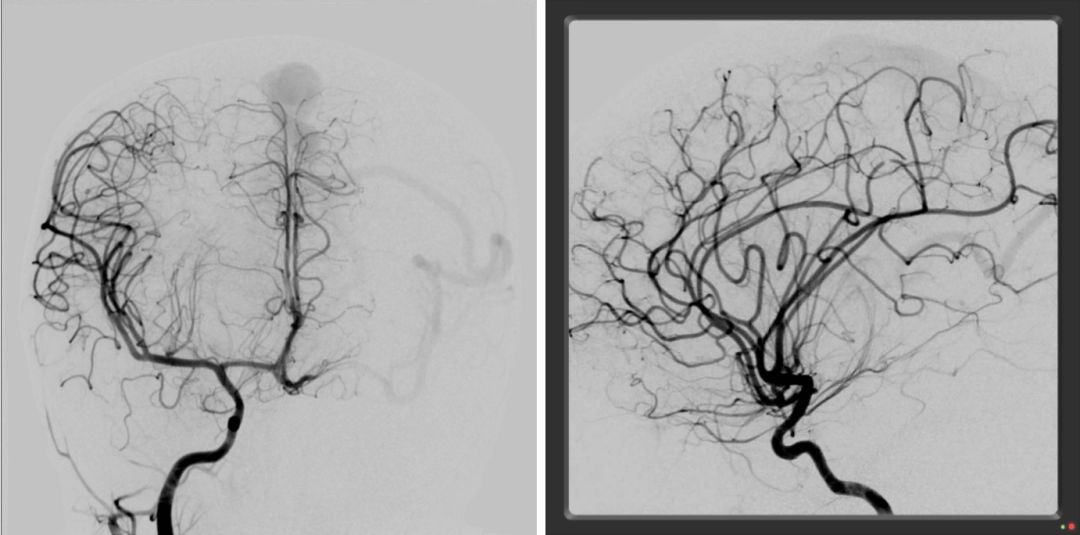

左侧大脑枕部动静脉畸形(未破裂)an unruptured bavm situated in the

枕深部动静脉畸形(图片展示)